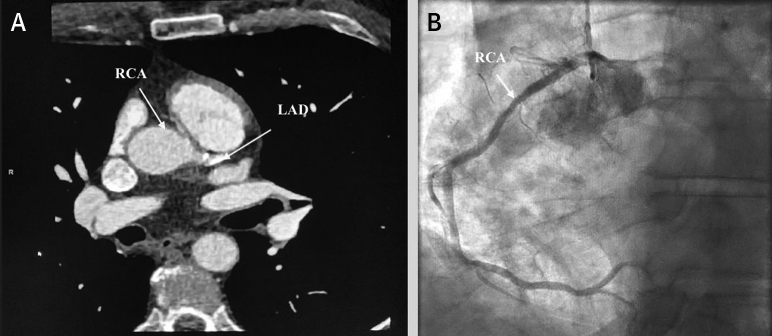

Figure 3.

CT of Coronary Artery and Angiography of Patient #2

(A) Chest CT demonstrating anomalous right coronary artery from the left coronary cusp. (B) Heart catherization of anomalous right coronary artery. Abbreviations as in Figure 1.

Multislice cardiac CT confirmed the ARCA from the left coronary cusp with interarterial course (Figure 3).